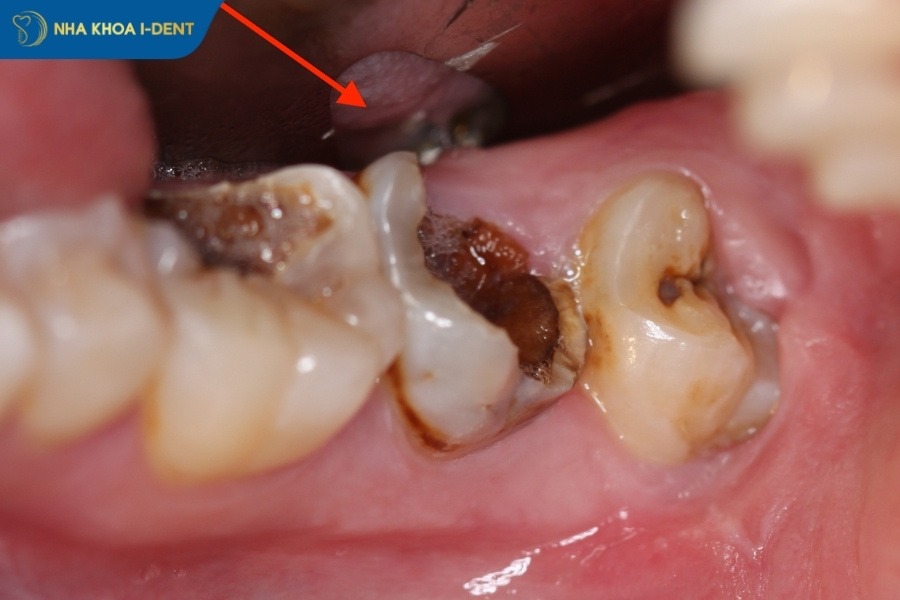

- Răng sâu nặng và cấu trúc răng bị phá hủy: Răng bị sâu vào tủy gây hoại tử và không thể phục hồi, chân răng bị tổn thương nghiêm trọng hoặc bị cụt.

- Răng sâu viêm nhiễm lan rộng: Răng sâu nặng bị vi khuẩn xâm nhập vào xương hàm, gây áp xe ổ răng, viêm nha chu hoặc tụt lợi nghiêm trọng.

Răng bị sâu nặng, mô răng mất nhiều và gây hoại tử nên nhổ răng.